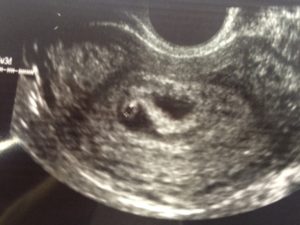

Плодное яйцо – овальное или круглое тело диаметром в несколько миллиметров. Диаметр плодного яйца замеряется во время первого же УЗИ. Учитывая его размеры, специалист может установить срок беременности. Но в некоторых случаях погрешность в определении составляет 1-1,5 недели. Поэтому врач, пытаясь установить срок, учитывает также показатели копчико-теменного размера.

плодное яйцо выглядит как образование в виде шара или овала. Уже в 5-6 недель желточный мешок, который обеспечивает питание эмбриона и выполняет кроветворную функцию на ранних стадиях развития эмбриона, похож на пузырек внутри полости плодного яйца.

Размер плодного яйца на этой стадии беременности составляет от 1,5 до 2,5 сантиметров. Рассмотреть зародыш в это время уже можно. Он выглядит, как пятимиллиметровая полоска, расположенная рядом с желточным мешком. И хотя определить, где у зародыша какая структура и часть пока невозможно, сердцебиение уже регистрируется.

Самый ранний срок, когда можно достоверно увидеть беременность на УЗИ, – пятая неделя.

Хороший врач на качественной аппаратуре сможет рассмотреть плодное яйцо, эмбрион в нем (он будет выглядеть как маленькая темная полоска длиной 3-5 мм), околоплодные воды; измерить его, оценить форму и прослушать сердцебиение эмбриона. Многоплодную беременность с уверенностью можно будет увидеть на более поздних сроках – примерно на 8-9 неделе.